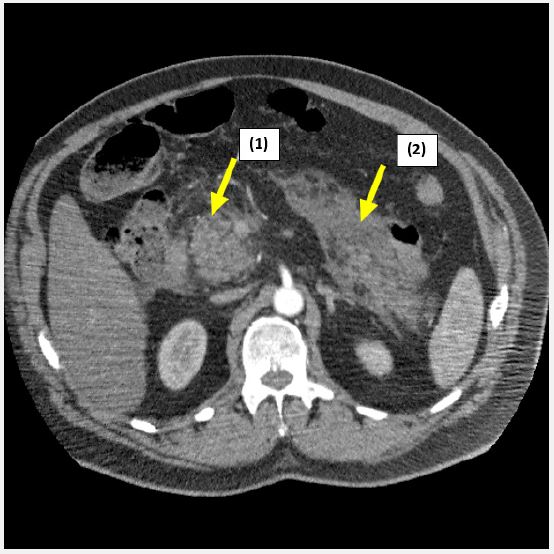

Clinical examination findings were as follows: blood pressure: 165/85 mmHg, heart rate: 90 bpm, SpO2: 97%, respiratory rate: 21. Pain relief was administered using morphine. Laboratory investigations revealed serum lipase of 331.1 U/L (normal <35 U/L). Initial ECG showed no abnormalities, and troponin levels were normal (0.037 ng/ml). CT imaging showed a mildly enlarged pancreas with peripancreatic infiltration, exudate and edema (Figure 1).

A diagnosis of acute pancreatitis was made, with no evidence of cardiac involvement. The patient was treated with Proton Pump Inhibitors (PPIs) and advised on diet and hydration in an outpatient setting due to refusal of hospitalization.